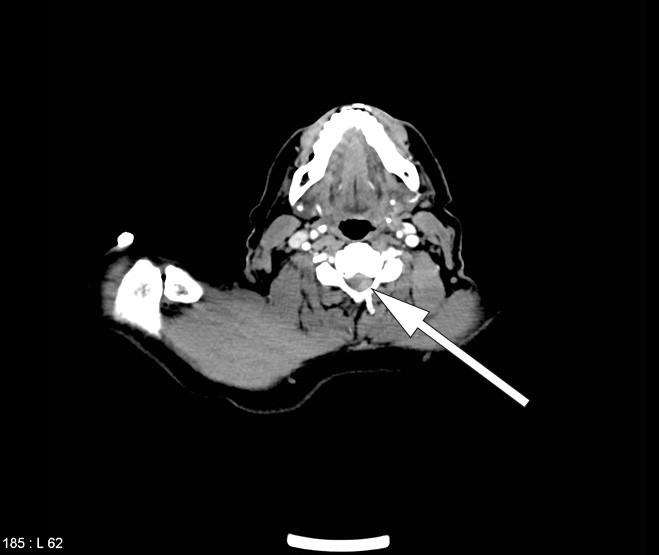

The CT scan of the total aorta on admission, prior to thrombolysis, was initially interpreted as normal, apart from a subtotal stenosis in the subclavian artery. However, a new examination of cervical sections with some change in the grey-tone scale (window/level) revealed that the epidural haemorrhage was already visible before the thrombolysis (Fig. 3).

Retrospective scrutiny of the CT total aorta showed that the epidural haemorrhage was already present before the thrombolysis (Fig. 3). It is therefore probable that this patient’s anterior spinal artery syndrome was caused by the epidural haemorrhage, and that the haemorrhage was not a complication caused by the treatment. It is possible, nonetheless, that it caused expansion of the haematoma. The fact that the patient experienced a transient improvement after the thrombolysis is difficult to explain, but may be due to the treatment causing the haematoma to spread in the epidural space, thereby slightly decompressing the spinal cord. The improvement was brief, and the patient rapidly deteriorated after thrombolysis. When the epidural haematoma was discovered, intervention took place swiftly. With haematomas that exert pressure on the spinal cord and cause neurological impairment, the prognosis depends on rapid surgical decompression (16, 19).